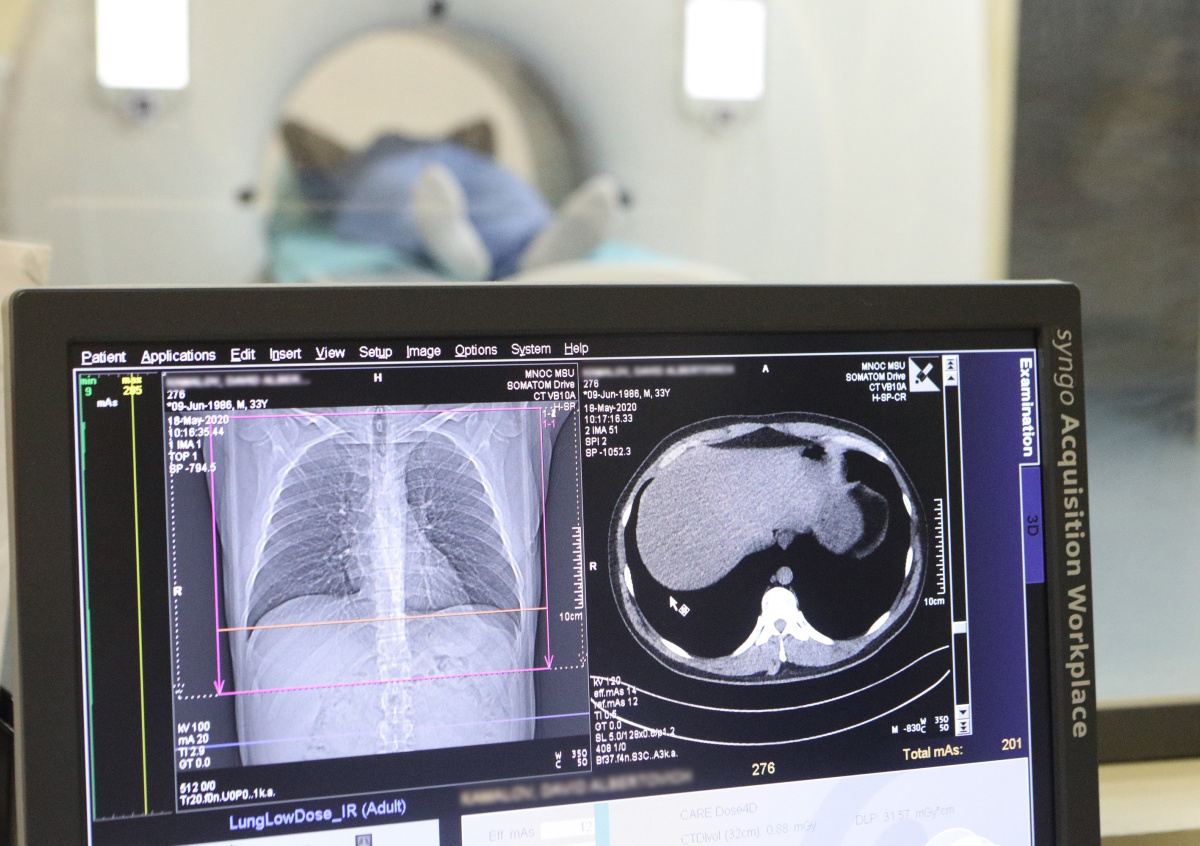

Когда нужно делать КТ: пульмонолог назвал главный и малоизвестный симптом

Проводить компьютерную томографию лёгких человеку нужно если у него на протяжении нескольких дней наблюдается температура, слабость, нарушение дыхательных функций и что наиболее важно — пониженное содержание кислорода в крови. Мало кто знает, но последний параметр человек может самостоятельно отследить в домашних условиях при помощи специального прибора пульсоксиметра, рассказал NEWS.ru профессор кафедры фтизиатрии и пульмонологии лечебного факультета МГМСУ Сергей Бабак.

Для этого достаточно наложить датчик на палец и ознакомиться с полученными данными на дисплее прибора. Нормальная насыщенность кислородом крови человека — от 96 до 99%, пояснил специалист. Если же показатель упал до 95%, то высока вероятность того, что человек заразился COVID-19 и после проведения КТ врачи обнаружат лёгочную форму коронавирусной инфекции. По итогам исследования компьютерный томограф выдаст цифру от одного до четырёх — она будет свидетельствовать об объёмах поражения лёгких. При значениях один и два пациента, возможно, попробуют полечить в домашних условиях. Цифры три и четыре будут говорить о том, что человеку требуется немедленная госпитализация, рассказал пульмонолог.

При этом, как отметил специалист, разговоры об опасности КТ несколько преувеличены. Если пациент находится в стационаре с тяжёлой пневмонией и врачам необходимо регулярно проверять структуру его лёгочной ткани, данная процедура может проводиться до пяти раз в месяц. Такая лучевая нагрузка считает предельно допустимой, если пациенту это необходимо.

Тем не менее, сверхвысокое рентгеновское излучение действительно может вызывать фиброз, пояснил профессор. Однако для того, чтобы с ним столкнуться, человеку придётся сделать около ста КТ в месяц.

Между тем, Бабак предупредил, что компьютерную томографию следует делать только по назначению врача.

КТ нельзя делать, если на это нет показаний и его вам не назначил врач. Только специалист может знать, нужно ли человеку данное исследование и нет ли у него противопоказаний. Компьютерная томография, к примеру, пагубно сказывается на процессе беременности, — пояснил в разговоре с NEWS.ru пульмонолог.